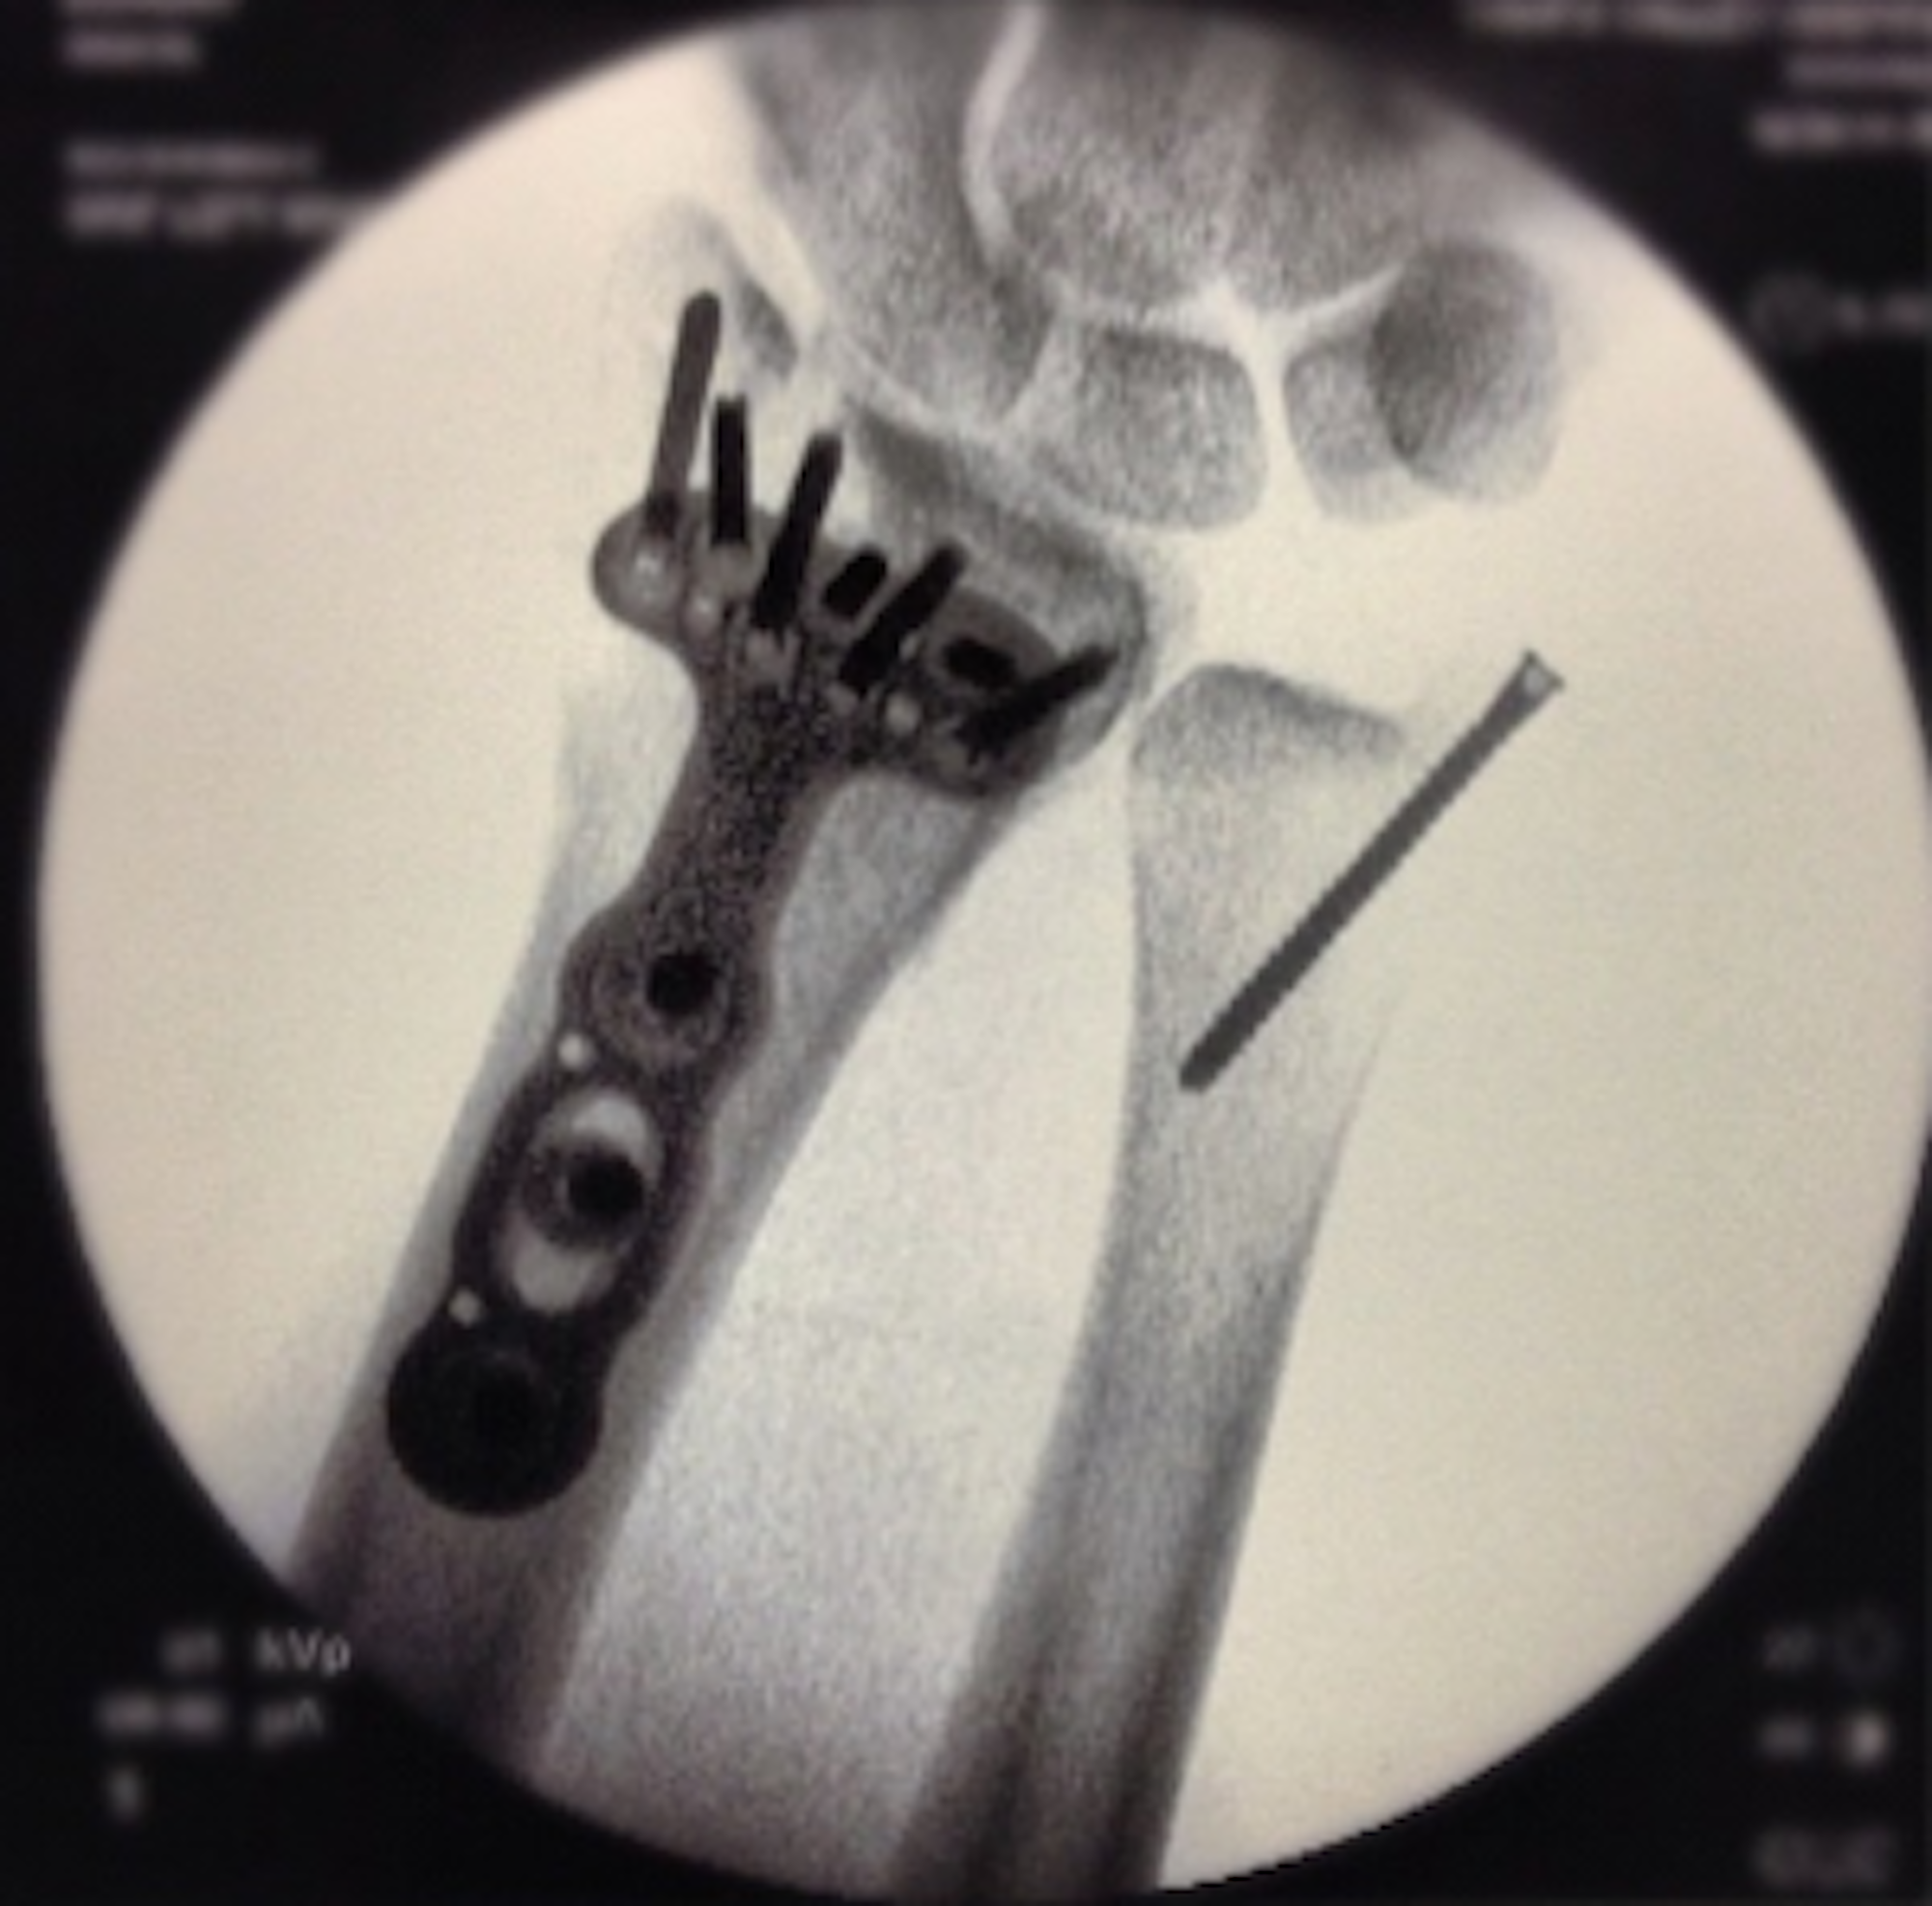

Simon Dumont, who is coming off of an ACL injury last March had been making great progress to being able to compete at the Dew Tour. Unfortunately, he suffered a wrist injury yesterday which required a 3-hour surgery last night.